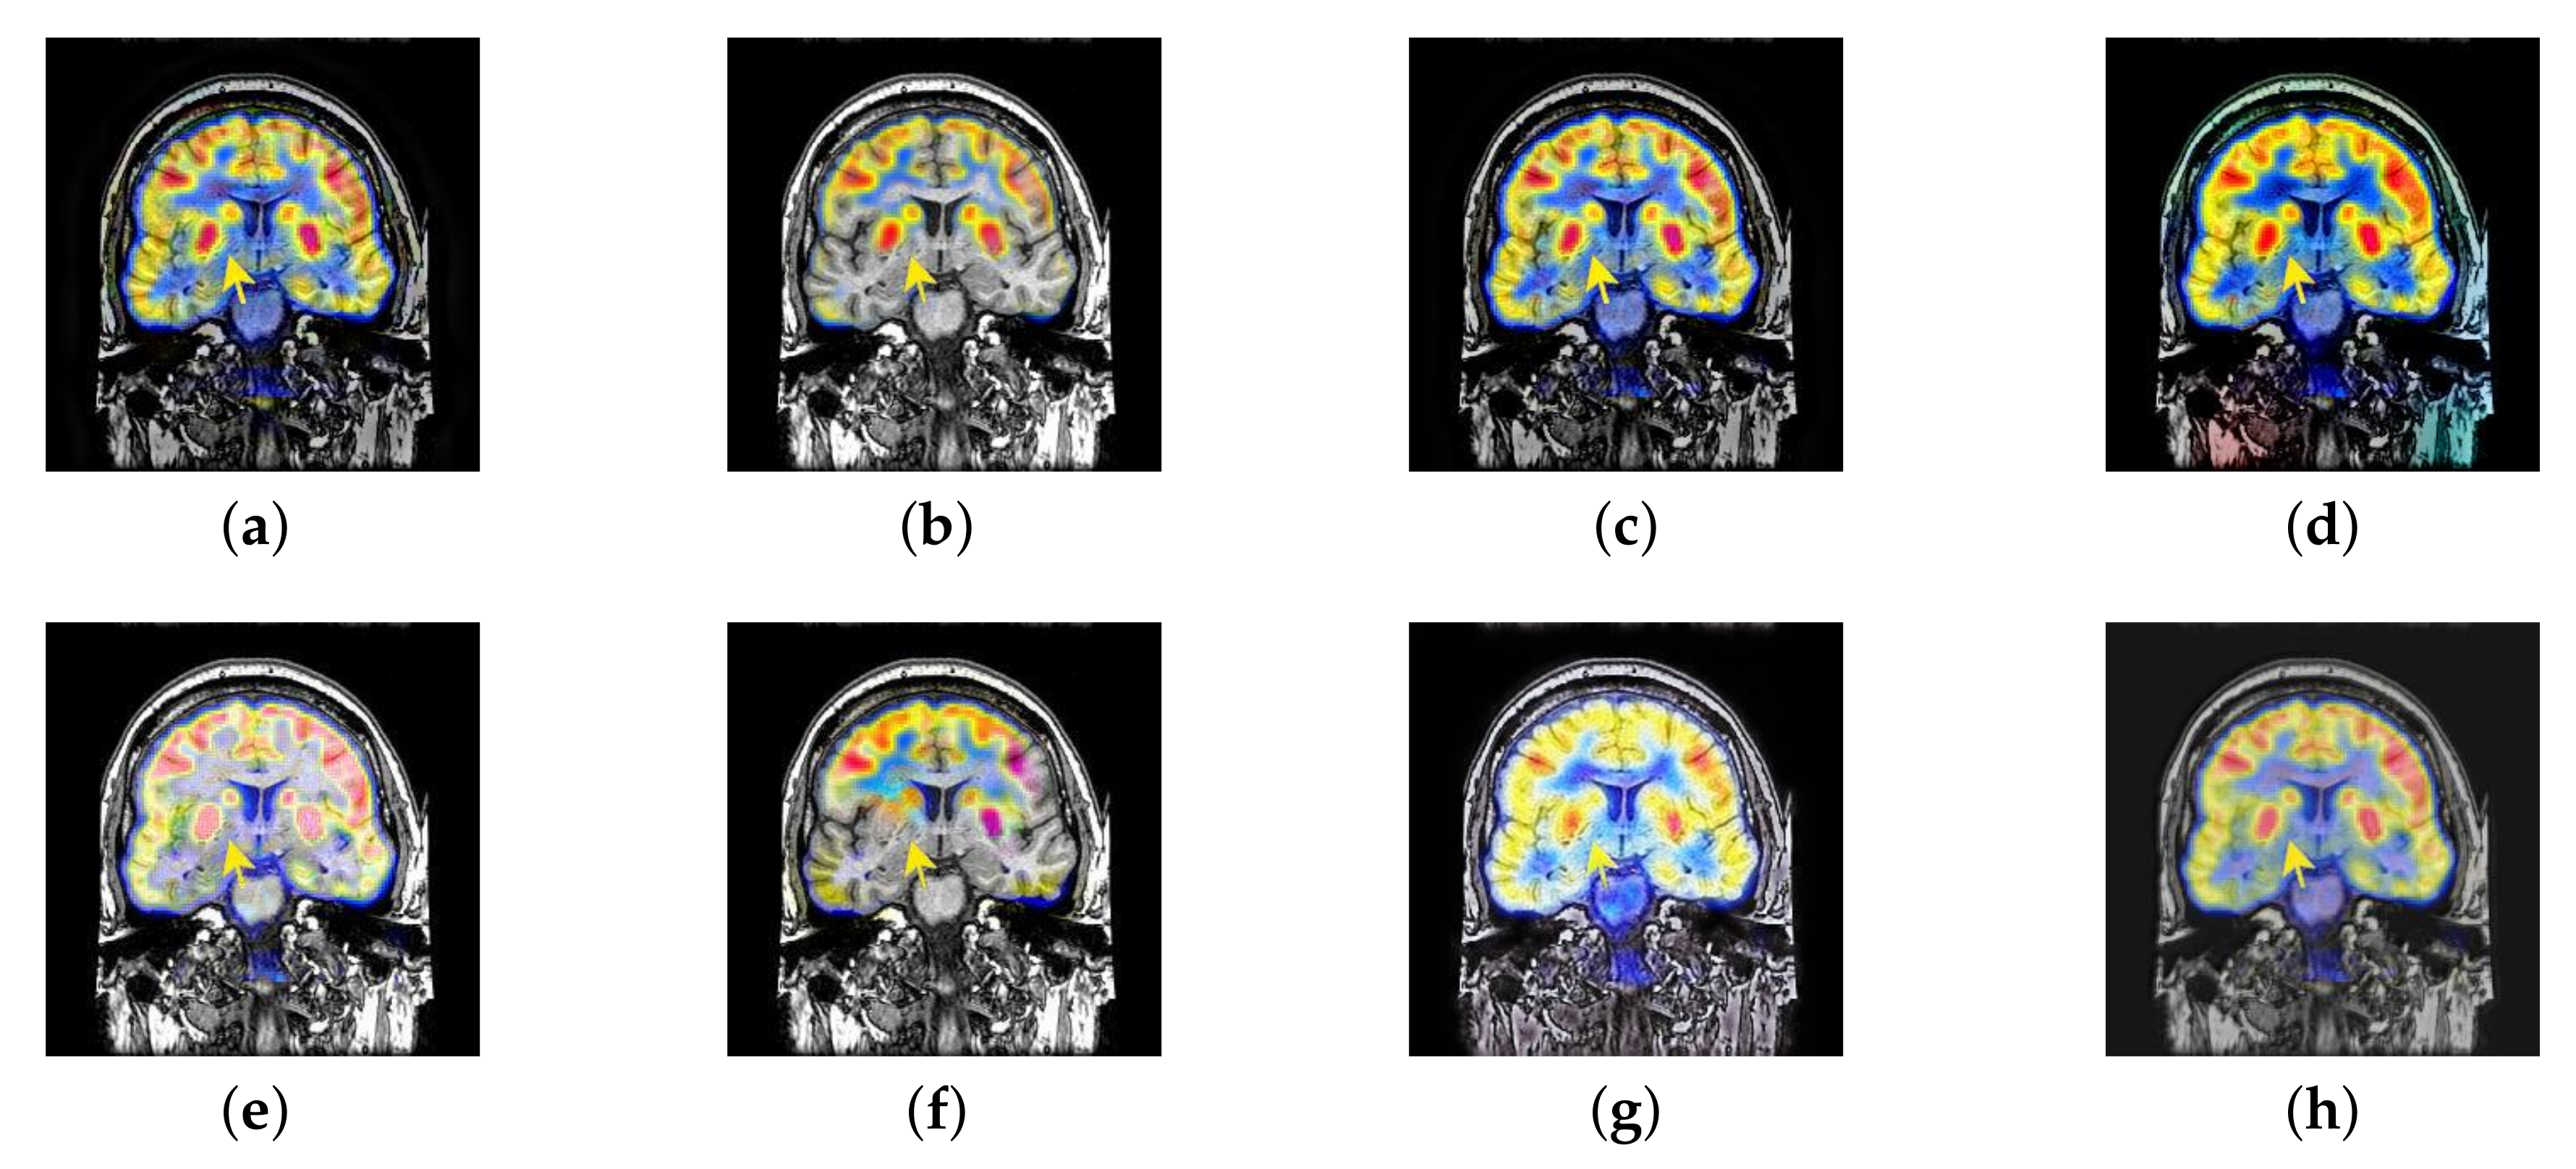

4.4. The Fusion of MRI-CBF

Cerebral blood flow diagram (CBF), which indicates the amount of blood flow in brain tissue with color. Red, yellow, green, blue, and black successively indicate the amount of blood flow from more to less. It is mainly used to detect the blood flow supply condition, elasticity, tension, and peripheral resistance. However, with the development of medical science, CBF image is often inferior in the diagnosis of brain diseases due to its lack of structural information. Therefore, MRI which is good at expressing structural information, is introduced to fuse in the current trend of brain medicine.

In this section, there are four image sets to fuse, each containing a MRI image and its corresponding CBF image in Figure 41. In Figure 42, Figure 43, Figure 44 and Figure 45, it can be seen that the structural information of fusion images obtained by our algorithm is complete. The color is not distorted, and the spectral features are natural. The fusion image based on DTCWT and NSCT algorithm have high color fidelity but less structural information. Other algorithms, such as IGM, LPSR, and FusionCNN, only focus on the structural information of the MRI image and ignore the color information of the fused image. Although the image structure information obtained by DDcGAN fusion algorithm is relatively complete, the edge of color information is not clear, which has a great influence on image contrast.

Figure 42.

Fused medical images obtained by different algorithms (Figure 41a,b): (a) DTCWT, (b) GFF, (c) NSCT, (d) LPSR, (e) IGM, (f) FusionCNN, (g) DDcGAN, and (h) FusionNet.

Figure 43.

Fused medical images obtained by different algorithms (Figure 41c,d): (a) DTCWT, (b) GFF, (c) NSCT, (d) LPSR, (e) IGM, (f) FusionCNN, (g) DDcGAN, and (h) FusionNet.

Figure 44.

Fused medical images obtained by different algorithms (Figure 41e,f): (a) DTCWT, (b) GFF, (c) NSCT, (d) LPSR, (e) IGM, (f) FusionCNN, (g) DDcGAN, and (h) FusionNet.

Figure 45.

Fused medical images obtained by different algorithms (Figure 41g,h): (a) DTCWT, (b) GFF, (c) NSCT, (d) LPSR, (e) IGM, (f) FusionCNN, (g) DDcGAN, and (h) FusionNet.